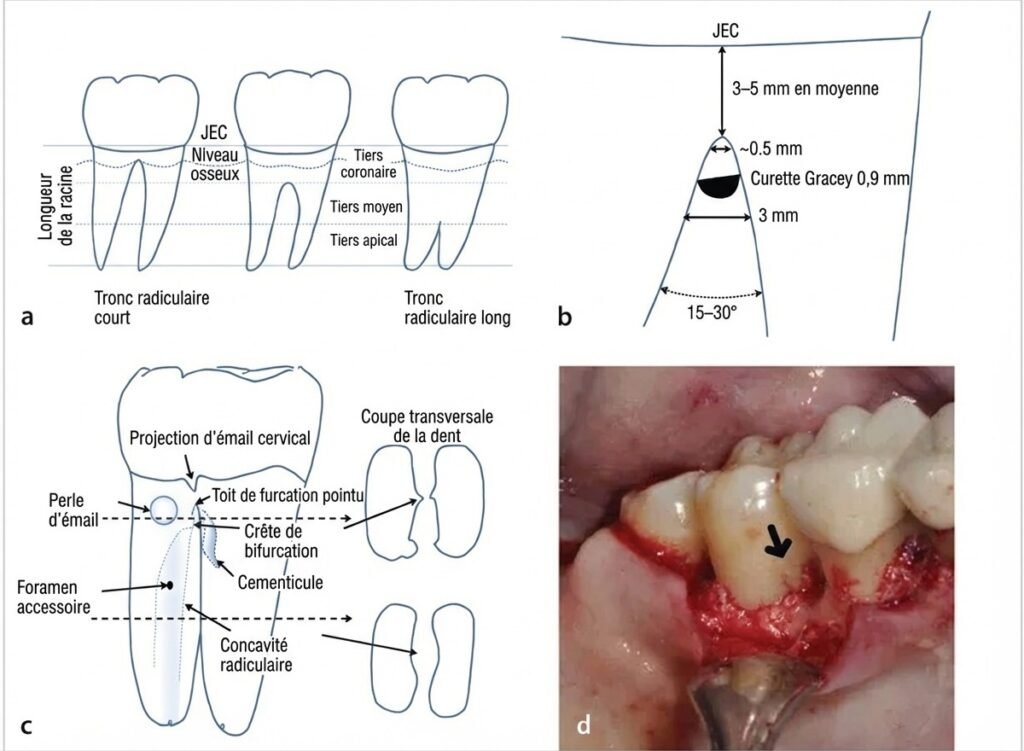

Le Tronc Radiculaire

Il correspond à la partie commune des racines, s’étendant de la jonction amélo-cémentaire (JAC) jusqu’à la furcation. On distingue trois types :

| Type de tronc | Longueur |

|---|---|

| Court | ≤ 1/3 de la hauteur radiculaire |

| Moyen | Entre 1/2 et 2/3 de la hauteur radiculaire |

| Long | > 2/3 de la hauteur radiculaire |

Un tronc court expose plus précocement la furcation en cas de perte d’attache, ce qui aggrave le pronostic. À l’inverse, un tronc long protège la furcation plus longtemps.

Facteurs Anatomiques

Plusieurs particularités morphologiques contribuent à la vulnérabilité de la furcation :

- Longueur du tronc cervical : Plus le tronc est court, plus la furcation est exposée précocement lors de la perte d’attache

- Concavités furcatoires et radiculaires : Zones de rétention de plaque, fréquentes sur les molaires mandibulaires, difficiles à instrumenter

- Largeur de l’espace interradiculaire : Plus l’espace est large et les racines divergentes, meilleure est la vascularisation et donc le potentiel de cicatrisation

- Arêtes et sillons furcatoires : Favorisent la colonisation bactérienne

Facteurs Embryologiques

- Projections d’émail (13 % des molaires) : l’absence d’attache conjonctive sur la surface amélaire crée une adhésion épithéliale vulnérable

- Perles d’émail : défauts d’attache conjonctive fragilisant l’herméticité de la jonction gingivo-dentaire